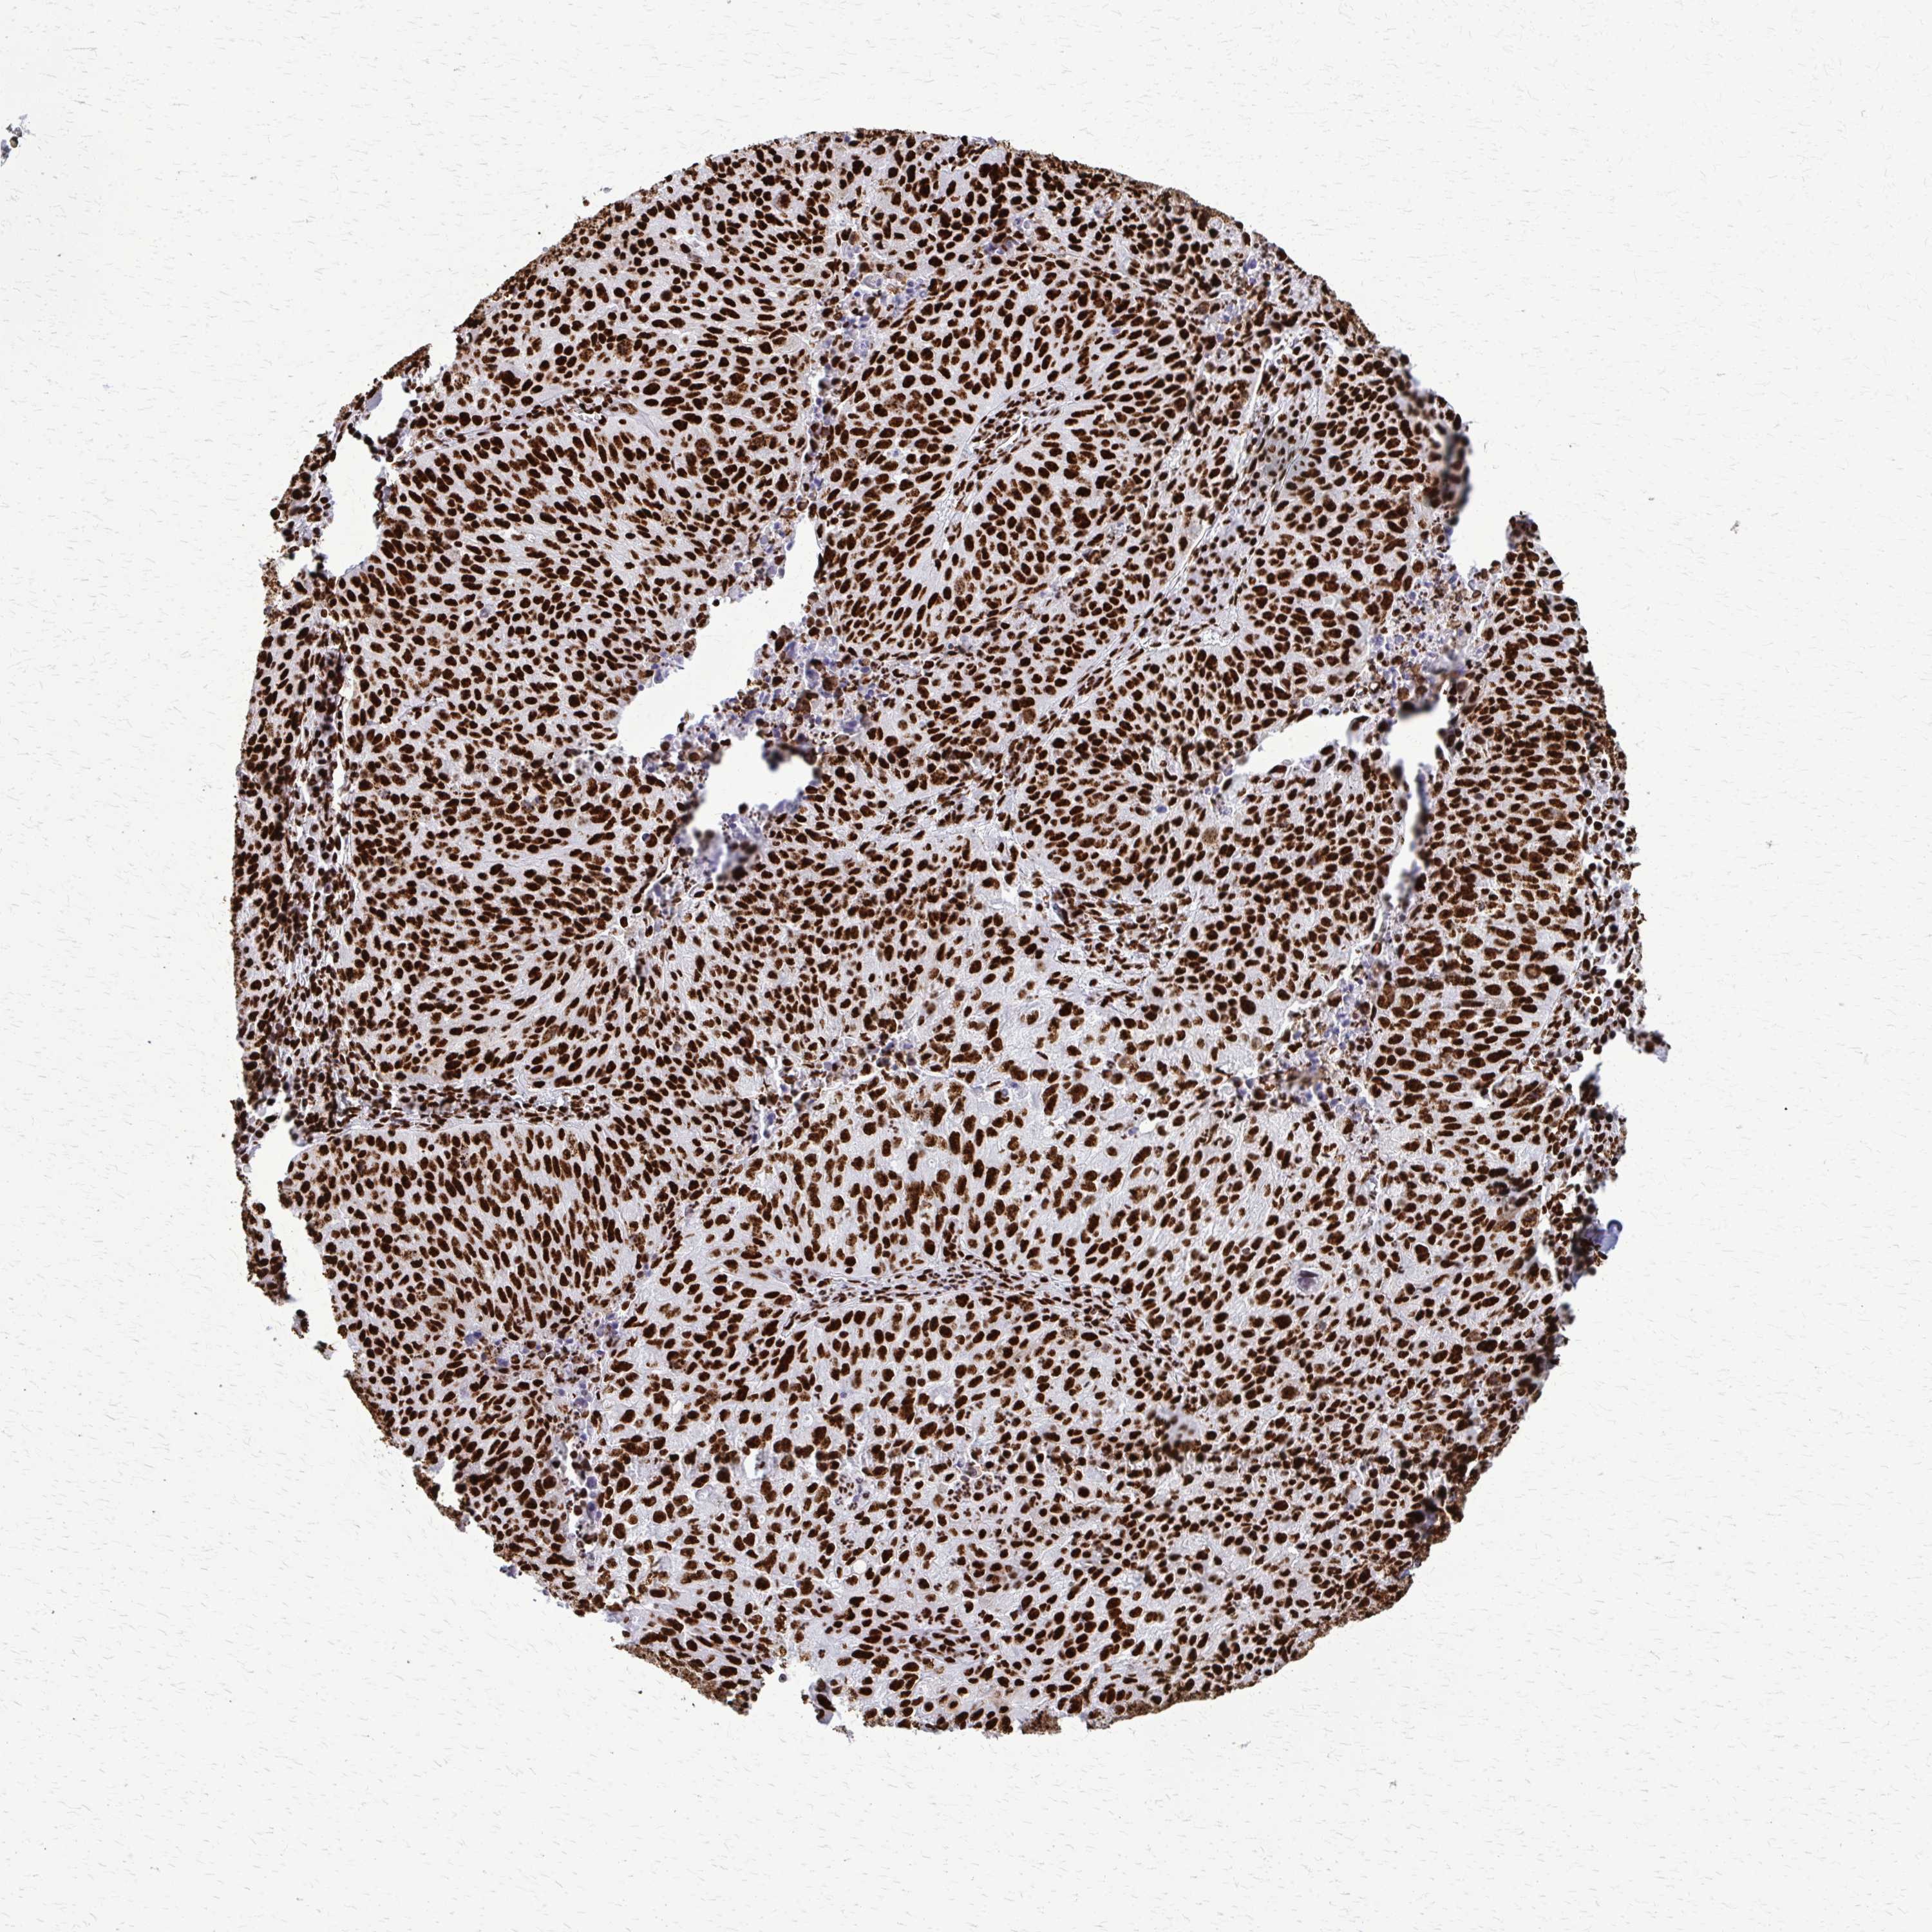

CANCER LUNG CANCER Show tissue menu

SFPQ is not prognostic in Lung Adenocarcinoma (TCGA)

: 73.8

Average pTPM 64.8

Number of samples 497